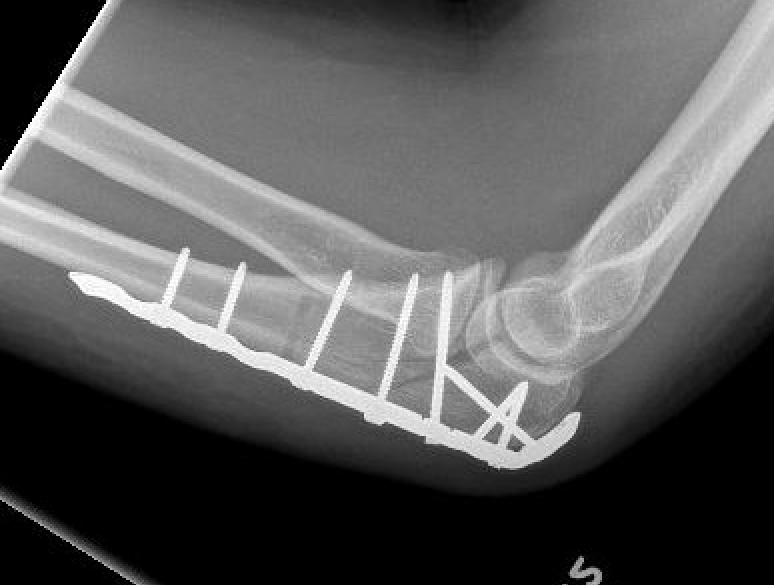

Technique

ORIF olecranon with plate +/- LCL repair

- posterior approach and plate olecranon

- reassess stability

- +/- Kocher approach to LCL and common extensor origin if continued instability